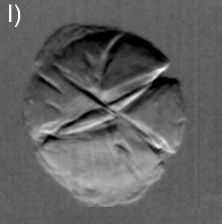

Dilute concentrations of precipitates without cores have also been observed, Figs. 3(e) and 3(f), as well as clinical cases of cataract with well-defined Y-sutures but with no distinct amounts of precipitates. In these cases, which correspond to 60% of the analyzed cases, there are significant scattering at the suture marks that can be generated either by local compaction of fiber cells or accumulation of precipitates along the marks, as for instance in Figs. 3(g) through 3(l). Refraction images show the extension of compaction areas while diffuse-scattering images can revel the presence or not of precipitates at the sutures. Absorption images (center of the analyzer window) provide essentially the same information of diffuse-scattering ones.